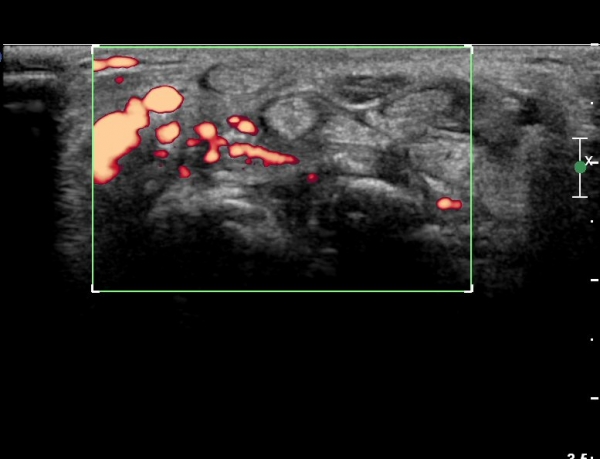

ÈûÁÙ ¹× Á¤Á߽ŰæÀÇ Ç¥ÃþÀ¸·Î ÀüÀ§°¡ °üÂûµÈ´Ù, (»çÁø 1 ), ÆÄ¿öµµÇ÷¯°Ë»ç¿¡¼ Ç÷·ùÁõ°¡°¡ °üÂûµÊ´Ù(»çÁø 2)..